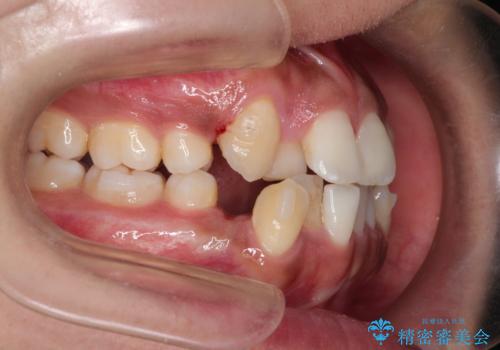

インビザラインと補助装置の併用による八重歯の抜歯矯正

- 八重歯を治したいとのことで来院されました。

重なりが強い右側の上下の歯を1本ずつ抜歯する計画としました。

インビザラインでの治療がご希望でしたが、右上の歯のかさなりが強いところは、補助装置である程度動かしてからインビザラインに移行することにしました。

下顎はインビザラインのみで治療を行いました。